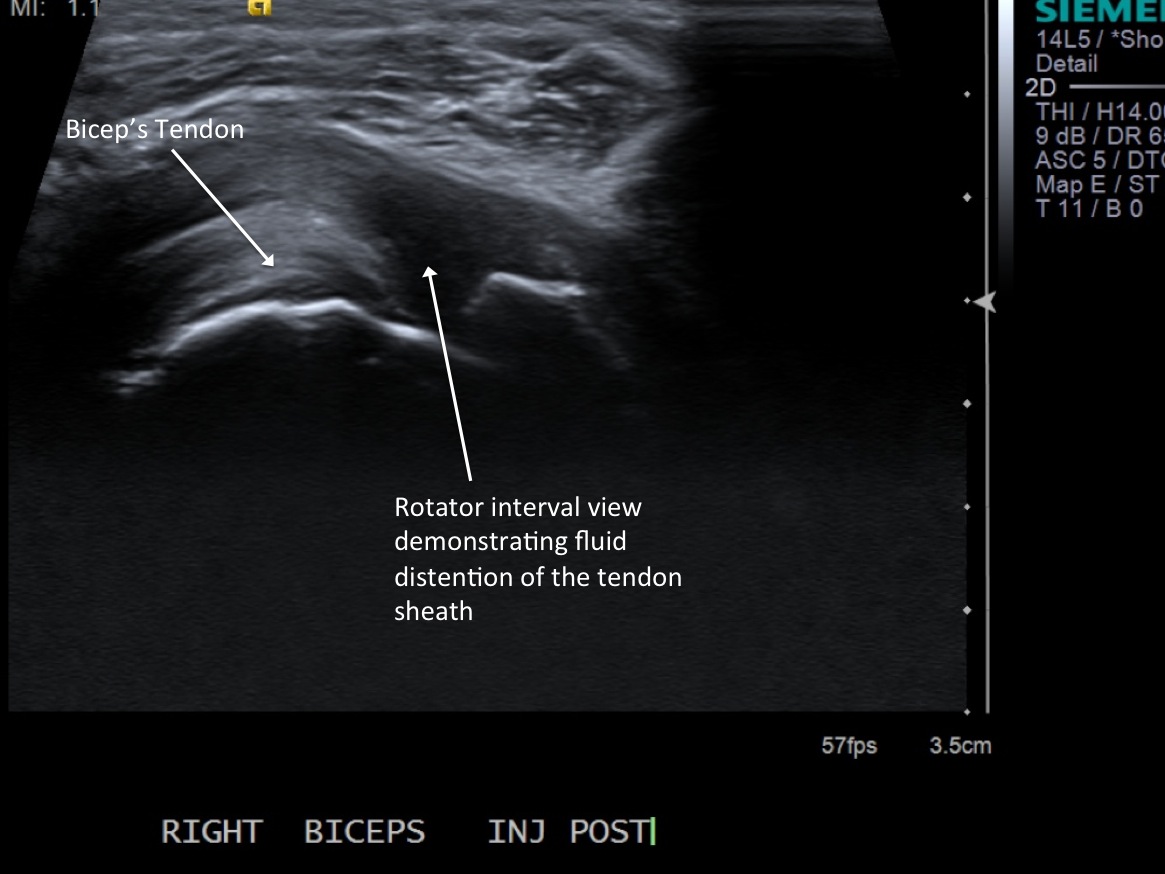

11. Test inject to see if easy flow with 1% lidocaine. If no resistance and see distention of the tendon sheath, exchange for 3cc syringe with injectable steroid and ropivacaine.

12. Scan sheath to demonstrate distention.

• descriptiondescription